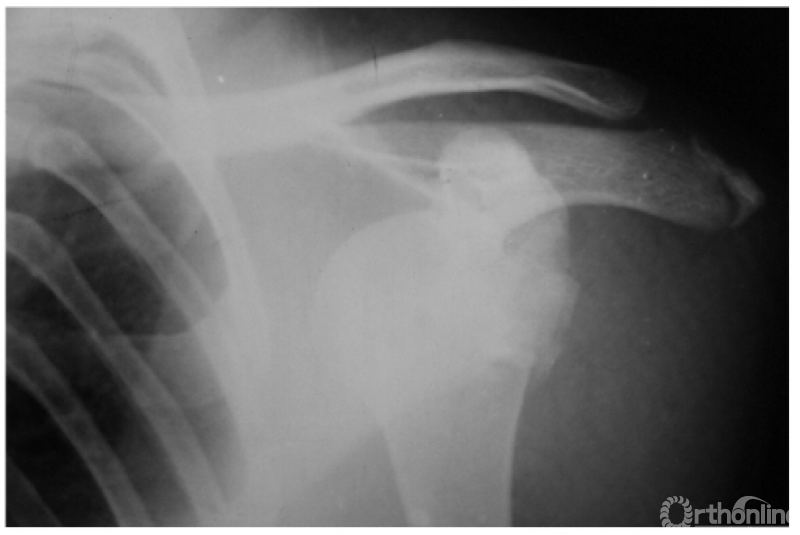

例3:肩关节喙突内下方脱位并大结节及肩峰端骨折(如下图)。